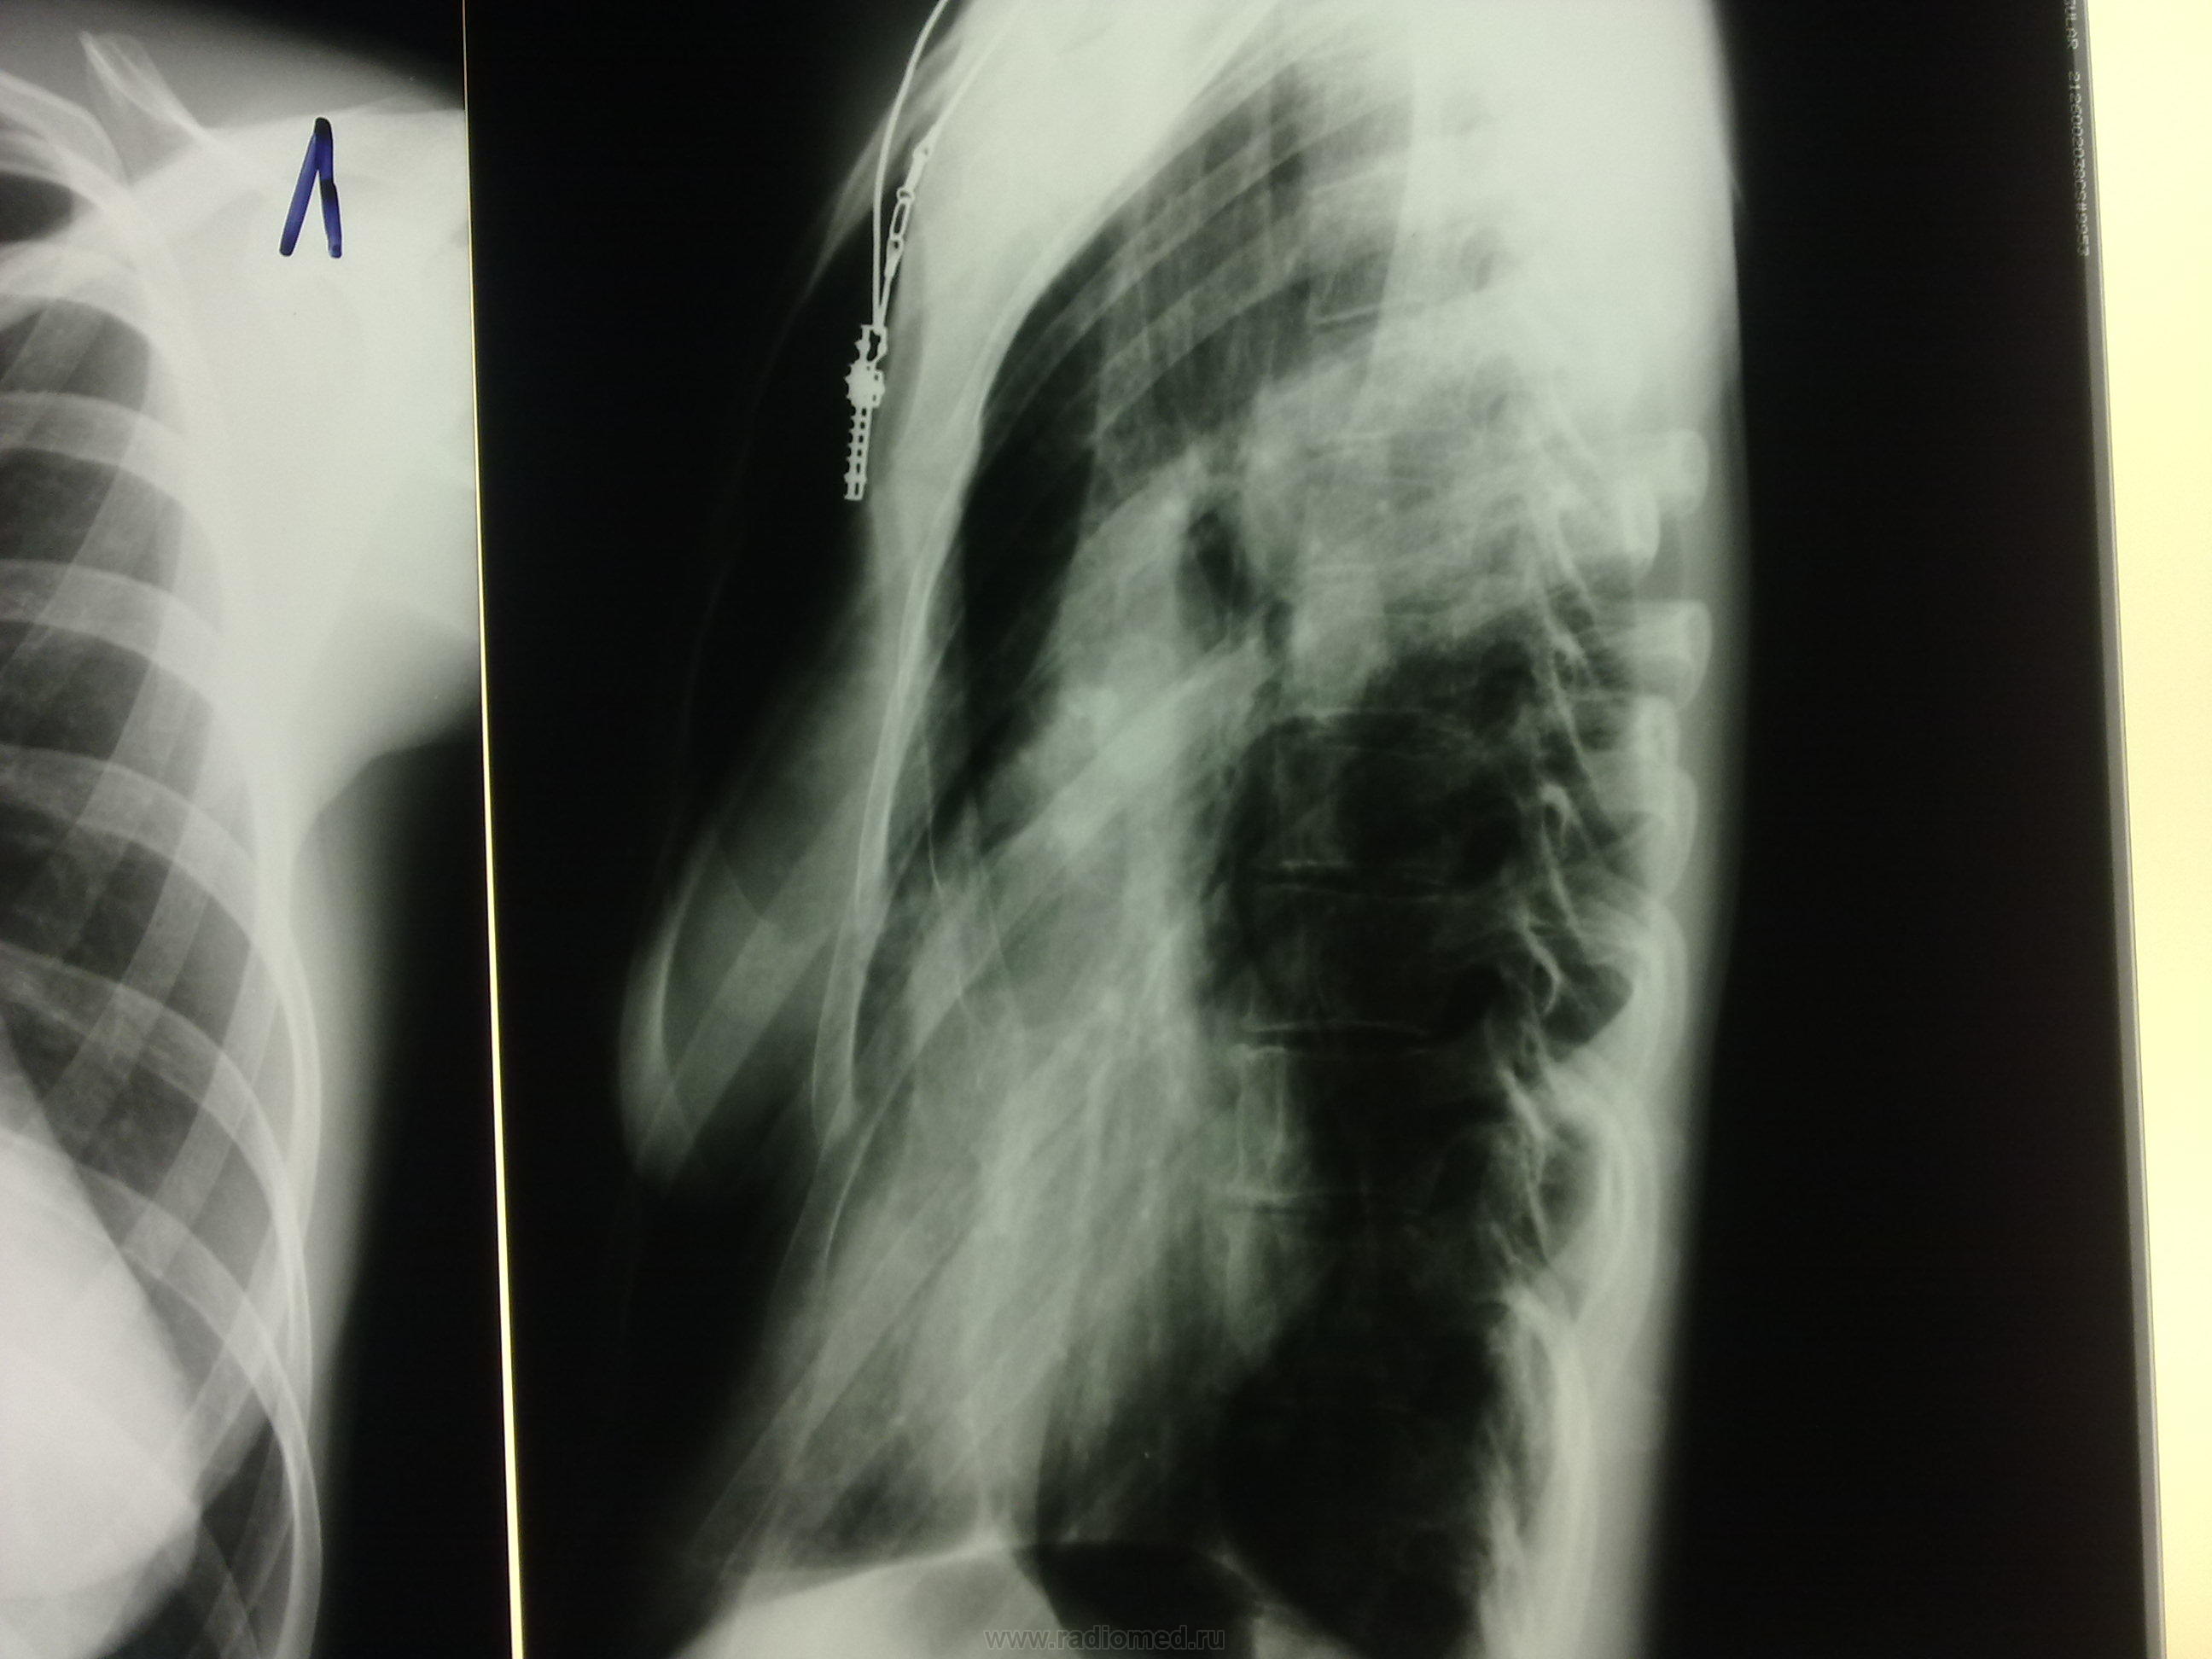

А, что смущает? Смещение сердца? При её комплекции, возможно и норма, или слегка развёрнута (грудинные концы ключиц не симметричные)

сложилась с тенью сердца - получилась такая картина;) а что тень сердца расширена таки напишите!

Плоская грудная клетка, молочная железа наслоилась на тень сердца. Боковая проекция - что то сильно развернута

какую хорошую укладку Вы хотите увидеть с такой деформацией грудной клетки и таким сколиозом